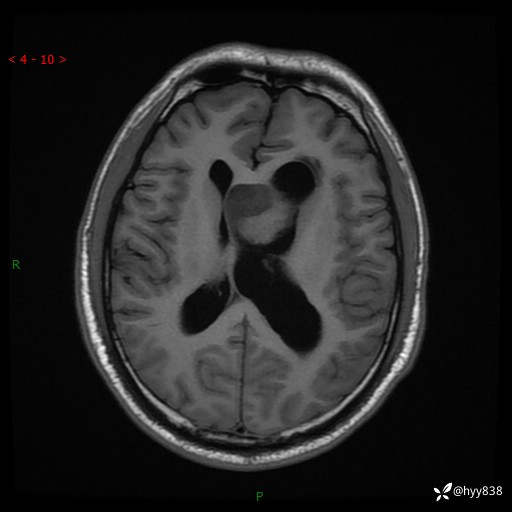

颅脑MRI平扫+增强